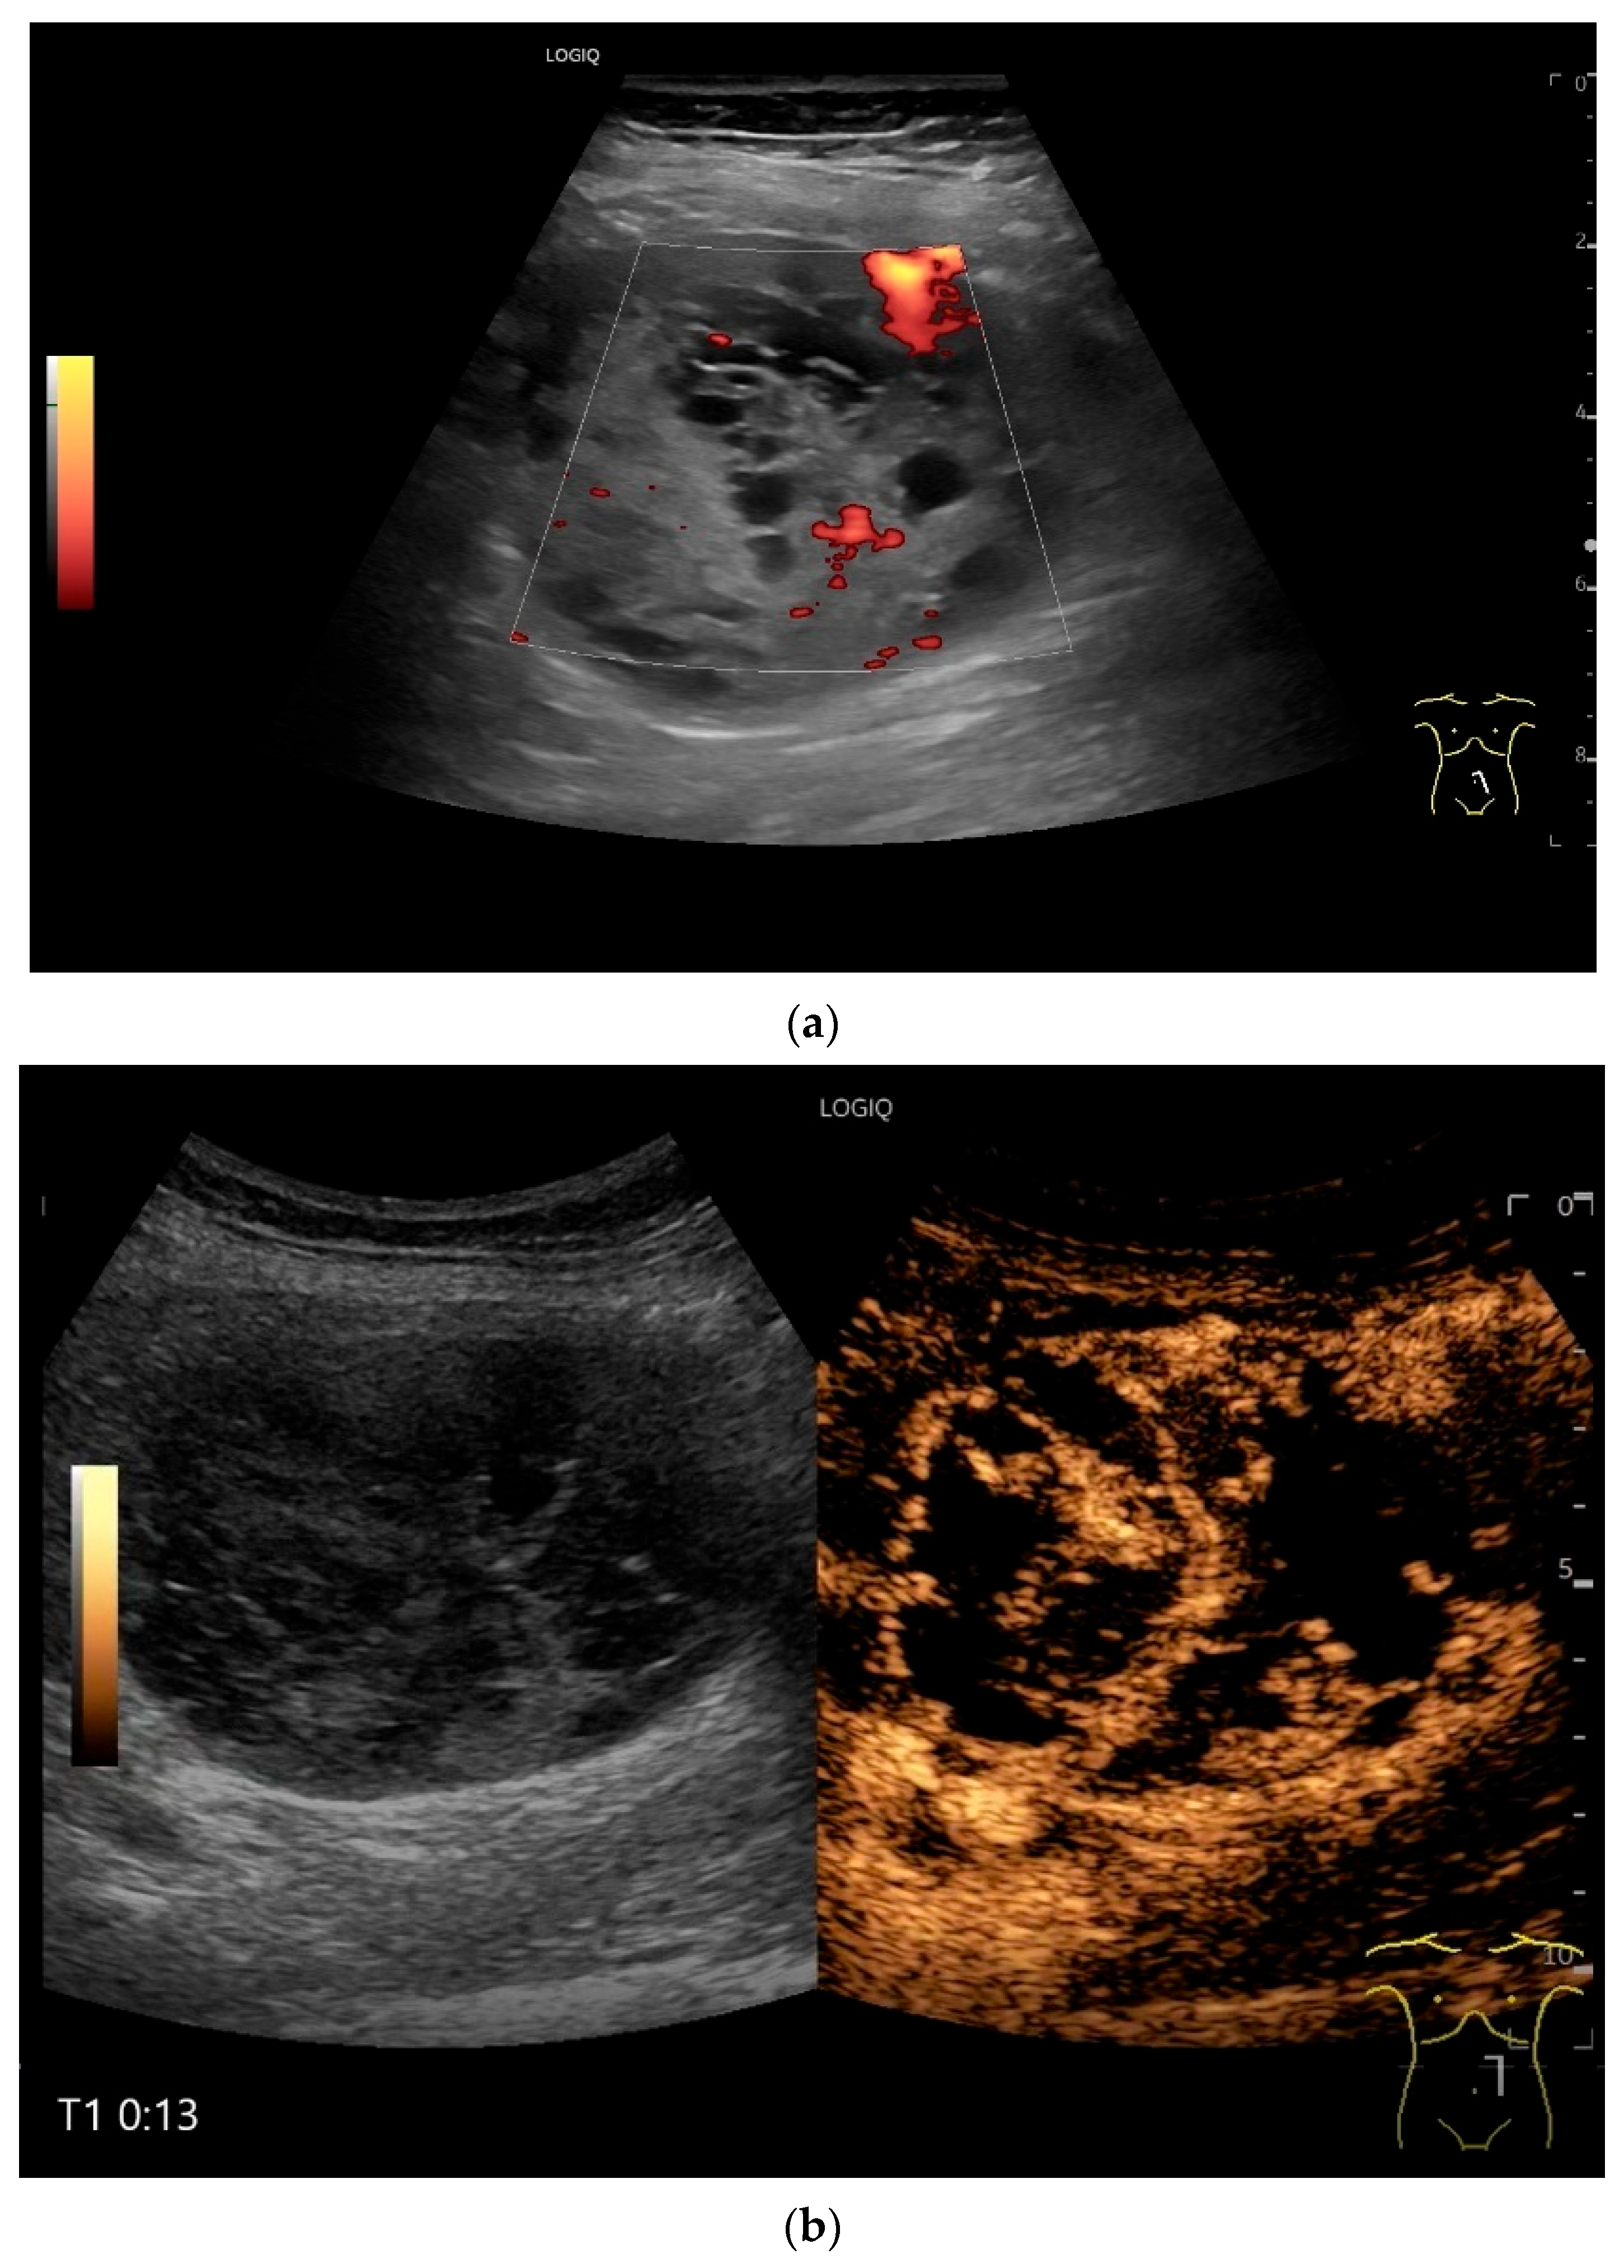

- Schwarze, V.; Marschner, C.; Grosu, S.; Rübenthaler, J.; Knösel, T.; Clevert, D.A. Modern sonographic imaging of abdominal neuroendocrine tumors. Radiologe 2019, 59, 1002–1009. [Google Scholar] [CrossRef] [PubMed]

- Zhao, J.Y.; Zhuang, H.; Luo, Y.; Su, M.G.; Xiong, M.L.; Wu, Y.T. Double contrast-enhanced ultrasonography of a small intestinal neuroendocrine tumor: A case report of a recommendable imaging modality. Precis. Clin. Med. 2020, 3, 147–152. [Google Scholar] [CrossRef]

| Neuroendocrine tumor | Small, nodular hypoechoic wall thickenings, mostly in the submucosa with spreading into the other layers. Usually with small vessels on CDI. Regionally enlarged lymph nodes. Multilocular manifestations are possible. |